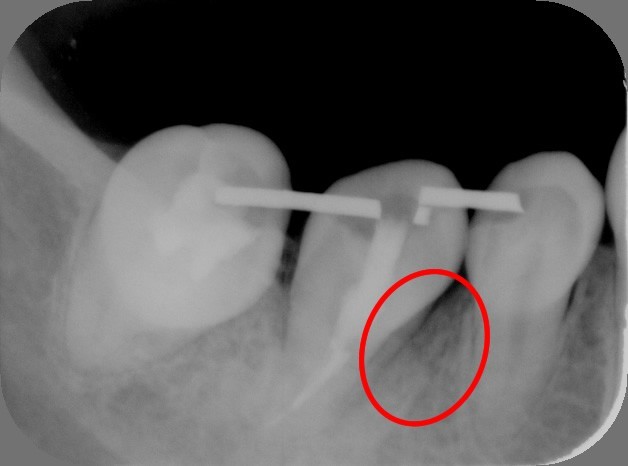

1.左から2番目が大きな虫歯で抜歯が必要です。